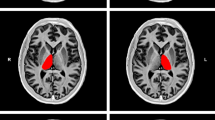

The DPN group had lower mean NAA:creatine ratios at long TE (median [range] 1.55 [1.14−1.95]; p = 0.04) than No-DPN participants (1.79 [1.22−2.20]) and healthy volunteers (1.90 [1.65−2.07]) (Table 1, Fig. 2a). NAA:choline ratio was also lowest in participants with DPN (1.55 [1.37−1.93]; p = 0.02) compared with No-DPN (1.80 [1.60−2.05]) and healthy volunteers (1.76 [1.58−1.86]) (Fig. 2b). The choline:creatine ratio obtained at long TE did not vary significantly between the groups (DPN 1.04 [0.84−1.23], No-DPN 0.95 [0.52−1.26], healthy volunteers 1.06 [0.89−1.25]; p = 0.87).

a N-Acetyl aspartate/creatine (NAA/Cr) and (b) N-acetyl aspartate/choline (NAA/Cho) ratios at long echo time in healthy volunteers (HV), diabetic patients with no neuropathy (No-DPN) and neuropathy (DPN). Horizontal lines represent group medians. Subgroup H-MRS metabolite differences (DPN vs No-DPN and HV) p = 0.04 (a), p = 0.02 (b)